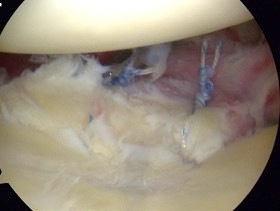

Arthroscopic

Arthroscopic suture anchor fixation anterior glenoid fracture

Anchor fixation